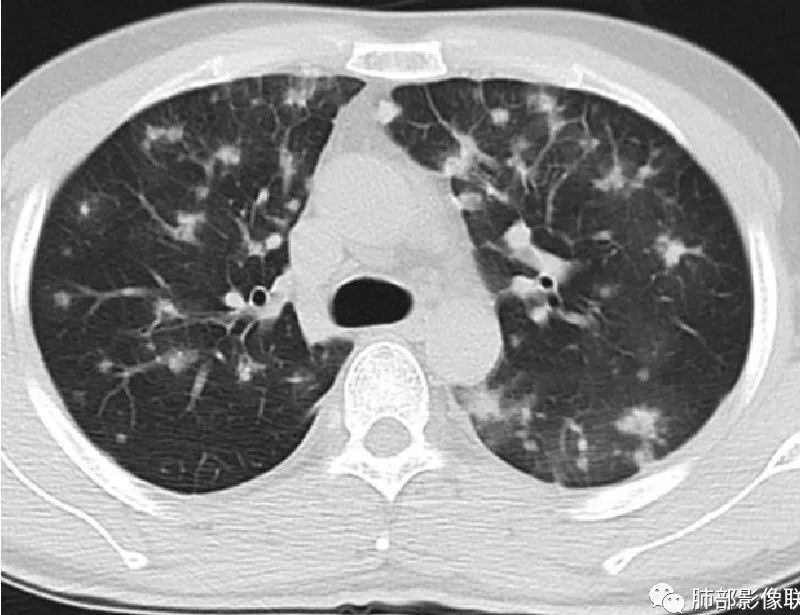

周一晚读病例:男性45岁,发热、纳差,全身散在暗紫色皮疹,结合CD4,符合HIV;肺部影像表现:两肺散在实性结节及磨玻璃密度影,实性结节伴晕征,部分沿支气管血管束分布,支气管血管束增粗,以两肺下叶为著,类似火焰征,双侧胸腔少量积液;首先考虑卡波西肉瘤,鉴别淋巴瘤增值性病变,淋巴瘤样肉芽肿/淋巴瘤,最后挂上马尔尼菲青霉菌病。

两肺弥漫性性结节状、小片状及片状带晕的病灶,煎蛋征、点晕征,主要分布两肺中下叶,病灶周围小叶间隔增厚呈网格状影,部分病灶累及胸膜,伴两侧胸膜增厚。

2.本例双肺小叶间隔增厚明显,多发结节影及片状实性密度影,沿血管支气管束分布为主,两侧较为对称,病灶多环以磨玻璃晕,边界不清。

双侧胸腔少量积液。双肺门及纵隔未见明确肿大淋巴结,纵隔结构间隙模糊。

3.有学者将这种具有沿双肺支气管束分布的实性密度片影描述为“火焰征”,认为具有一定特征性,单就影像表现而言,这种影像表现也可以见于其他病损或多种病理改变的叠加。

1.结节型:两肺沿支气管血管束分布的结节影,呈火焰状或星芒状、挂果征,局部周围出血磨玻璃影(肺泡出血或水肿)。

2.支气管血管束增粗型:

肺门周围支气管壁呈“套袖样”改变。

3.肺炎渗出型:

斑片渗出影,部分融合呈“火焰样”,同时有火焰样结节,小叶间隔增厚等表现。

还可以有纵隔及腋下淋巴结增大,胸腔积液等表现。